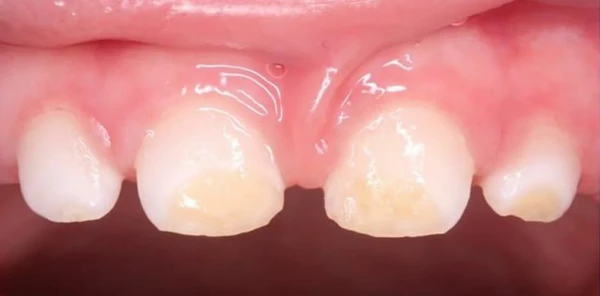

Слабая степень недоразвития эмали проявляется в виде пятен чаще белого, реже желтоватого цвета, с чёткими границами и одинаковой величины на одноимённых зубах. Пятна обычно обнаруживаются на вестибулярной поверхности и не сопровождаются какими-либо неприятными ощущениями. Пятна при гипоплазии не окрашиваются красителями (в отличие от кариеса в стадии пятна).

Проявляется местная гипоплазия в виде беловато-желтоватых пятен, углублений, располагающихся на всех поверхностях. В тяжёлых случаях может быть аплазия (отсутствие) эмали.